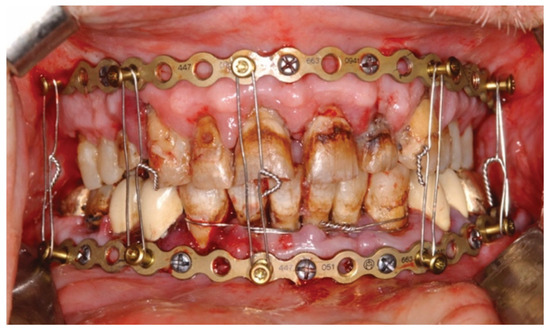

3.2. Matrix WaveTM Plate MMF System—Mode of Application

3.3. ‘In-Situ-Bending’ for Fracture Reduction